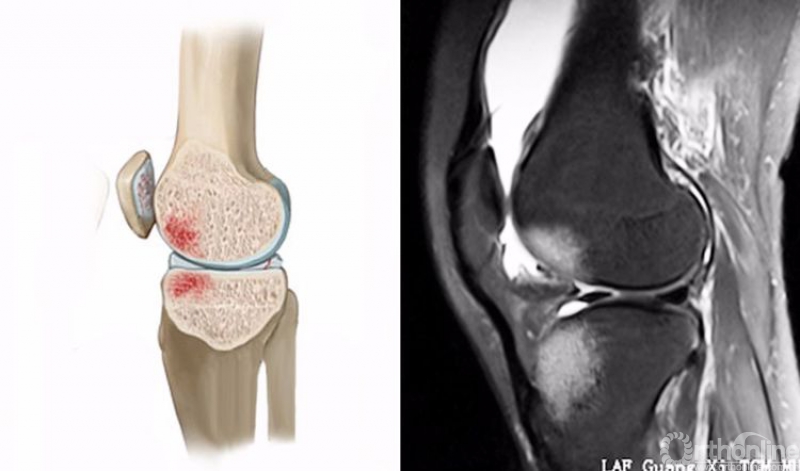

1.轴移损伤(pivot-shift injury)

膝关节在不同程度的屈曲和胫骨外旋或股骨内旋状态下,受到外翻力的作用。通常在快速减速并改变方向的时侯发生前交叉韧带(ACL)撕裂,一旦ACL撕裂,胫骨就相对于股骨前移,使股骨外侧髁和胫骨外后方撞击。其屈曲的程度决定股骨髁挫伤的部位。

膝关节轴移损伤在MRI上主要表现为股骨外侧髁和胫骨外后方骨髓水肿,T2WI及STIR像呈高信号改变,一般预示着ACL损伤。